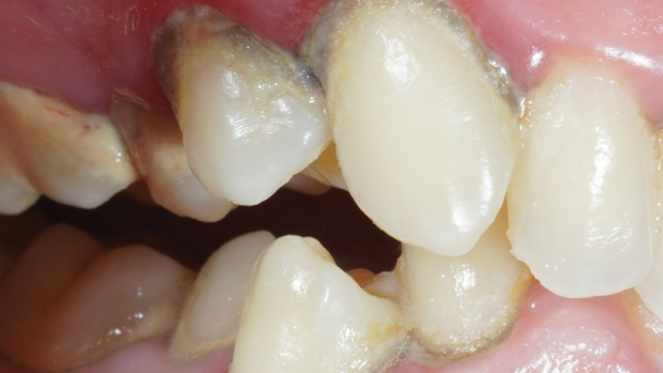

Пародонтит тяжелой степени

Результат через 2 недели

Параметры изменяются в зависимости от процедуры